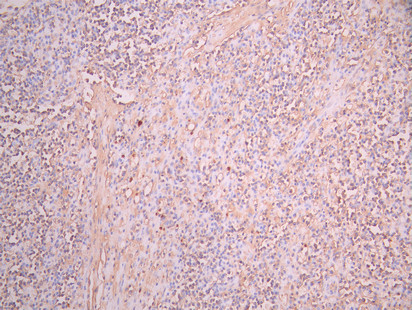

• IHC image of CSB-RA006243MA1HU diluted at 1:50 and staining in paraffin-embedded human lymph node tissue performed on a Leica BondTM system. After dewaxing and hydration, antigen retrieval was mediated by high pressure in a citrate buffer (pH 6.0). Section was blocked with 10% normal goat serum 30min at RT. Then primary antibody (1% BSA) was incubated at 4°C overnight. The primary is detected by a Anti-Human lgG, Fcy Fragment Specific labeled by HRP and visualized using 0.05% DAB.